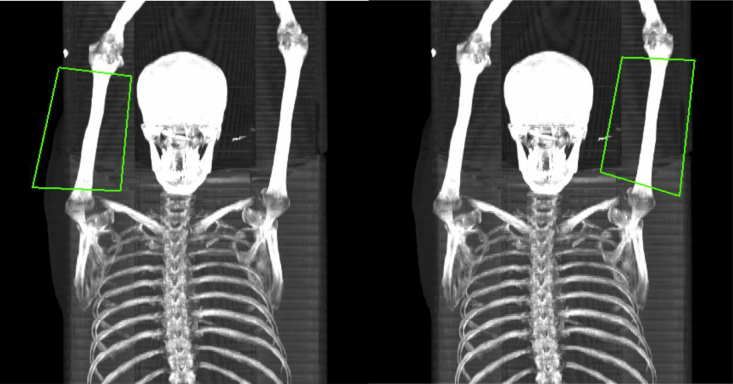

Objective: This study aimed to introduce a computed tomography (CT)-based tissue segmentation technique to quantify the volume and metabolic activity of the arm muscles using [ 18 F]-fluorodeoxyglucose ([ 18 F]FDG) PET/CT.

Methods: Eighty-seven subjects from the CAMONA study were included. A semiautomated three-dimensional segmentation algorithm was used to highlight the muscle. The [ 18 F]FDG uptake was measured as mean standardized uptake value (SUV) normalized to body weight (SUV BW ) and to lean body mass (SUV LBM ). To acquire normalized volume, arm muscle volume, humerus volume, and humerus length were used. The average SUV mean was calculated from independently measured volumes (cm 3 ) of the left and right muscle groups. The obtained SUV BW , SUV LBM , and normalized volume were used to compare the right and left arms.